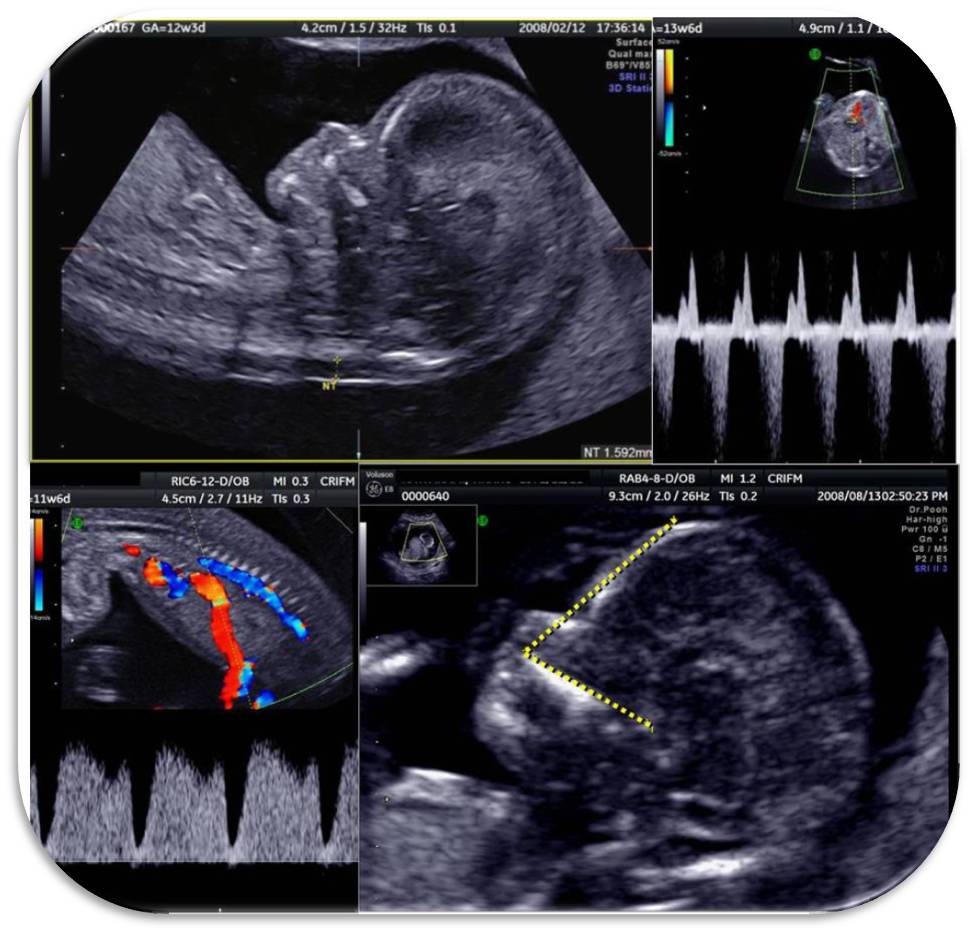

超音波検査 古賀文敏ウイメンズクリニック

第2回nt理論 実践セミナー 11 13週スキャンコース 2009 日本イアンドナルド超音波講座

胎児エコーの最新動向 新 超音波診断 Vol 02 東芝メディカルシステムズ株式会社 Innavi Suite

胎児エコーの最新動向 新 超音波診断 Vol 02 東芝メディカルシステムズ株式会社 Innavi Suite

初期ドック クリフム夫律子マタニティクリニック